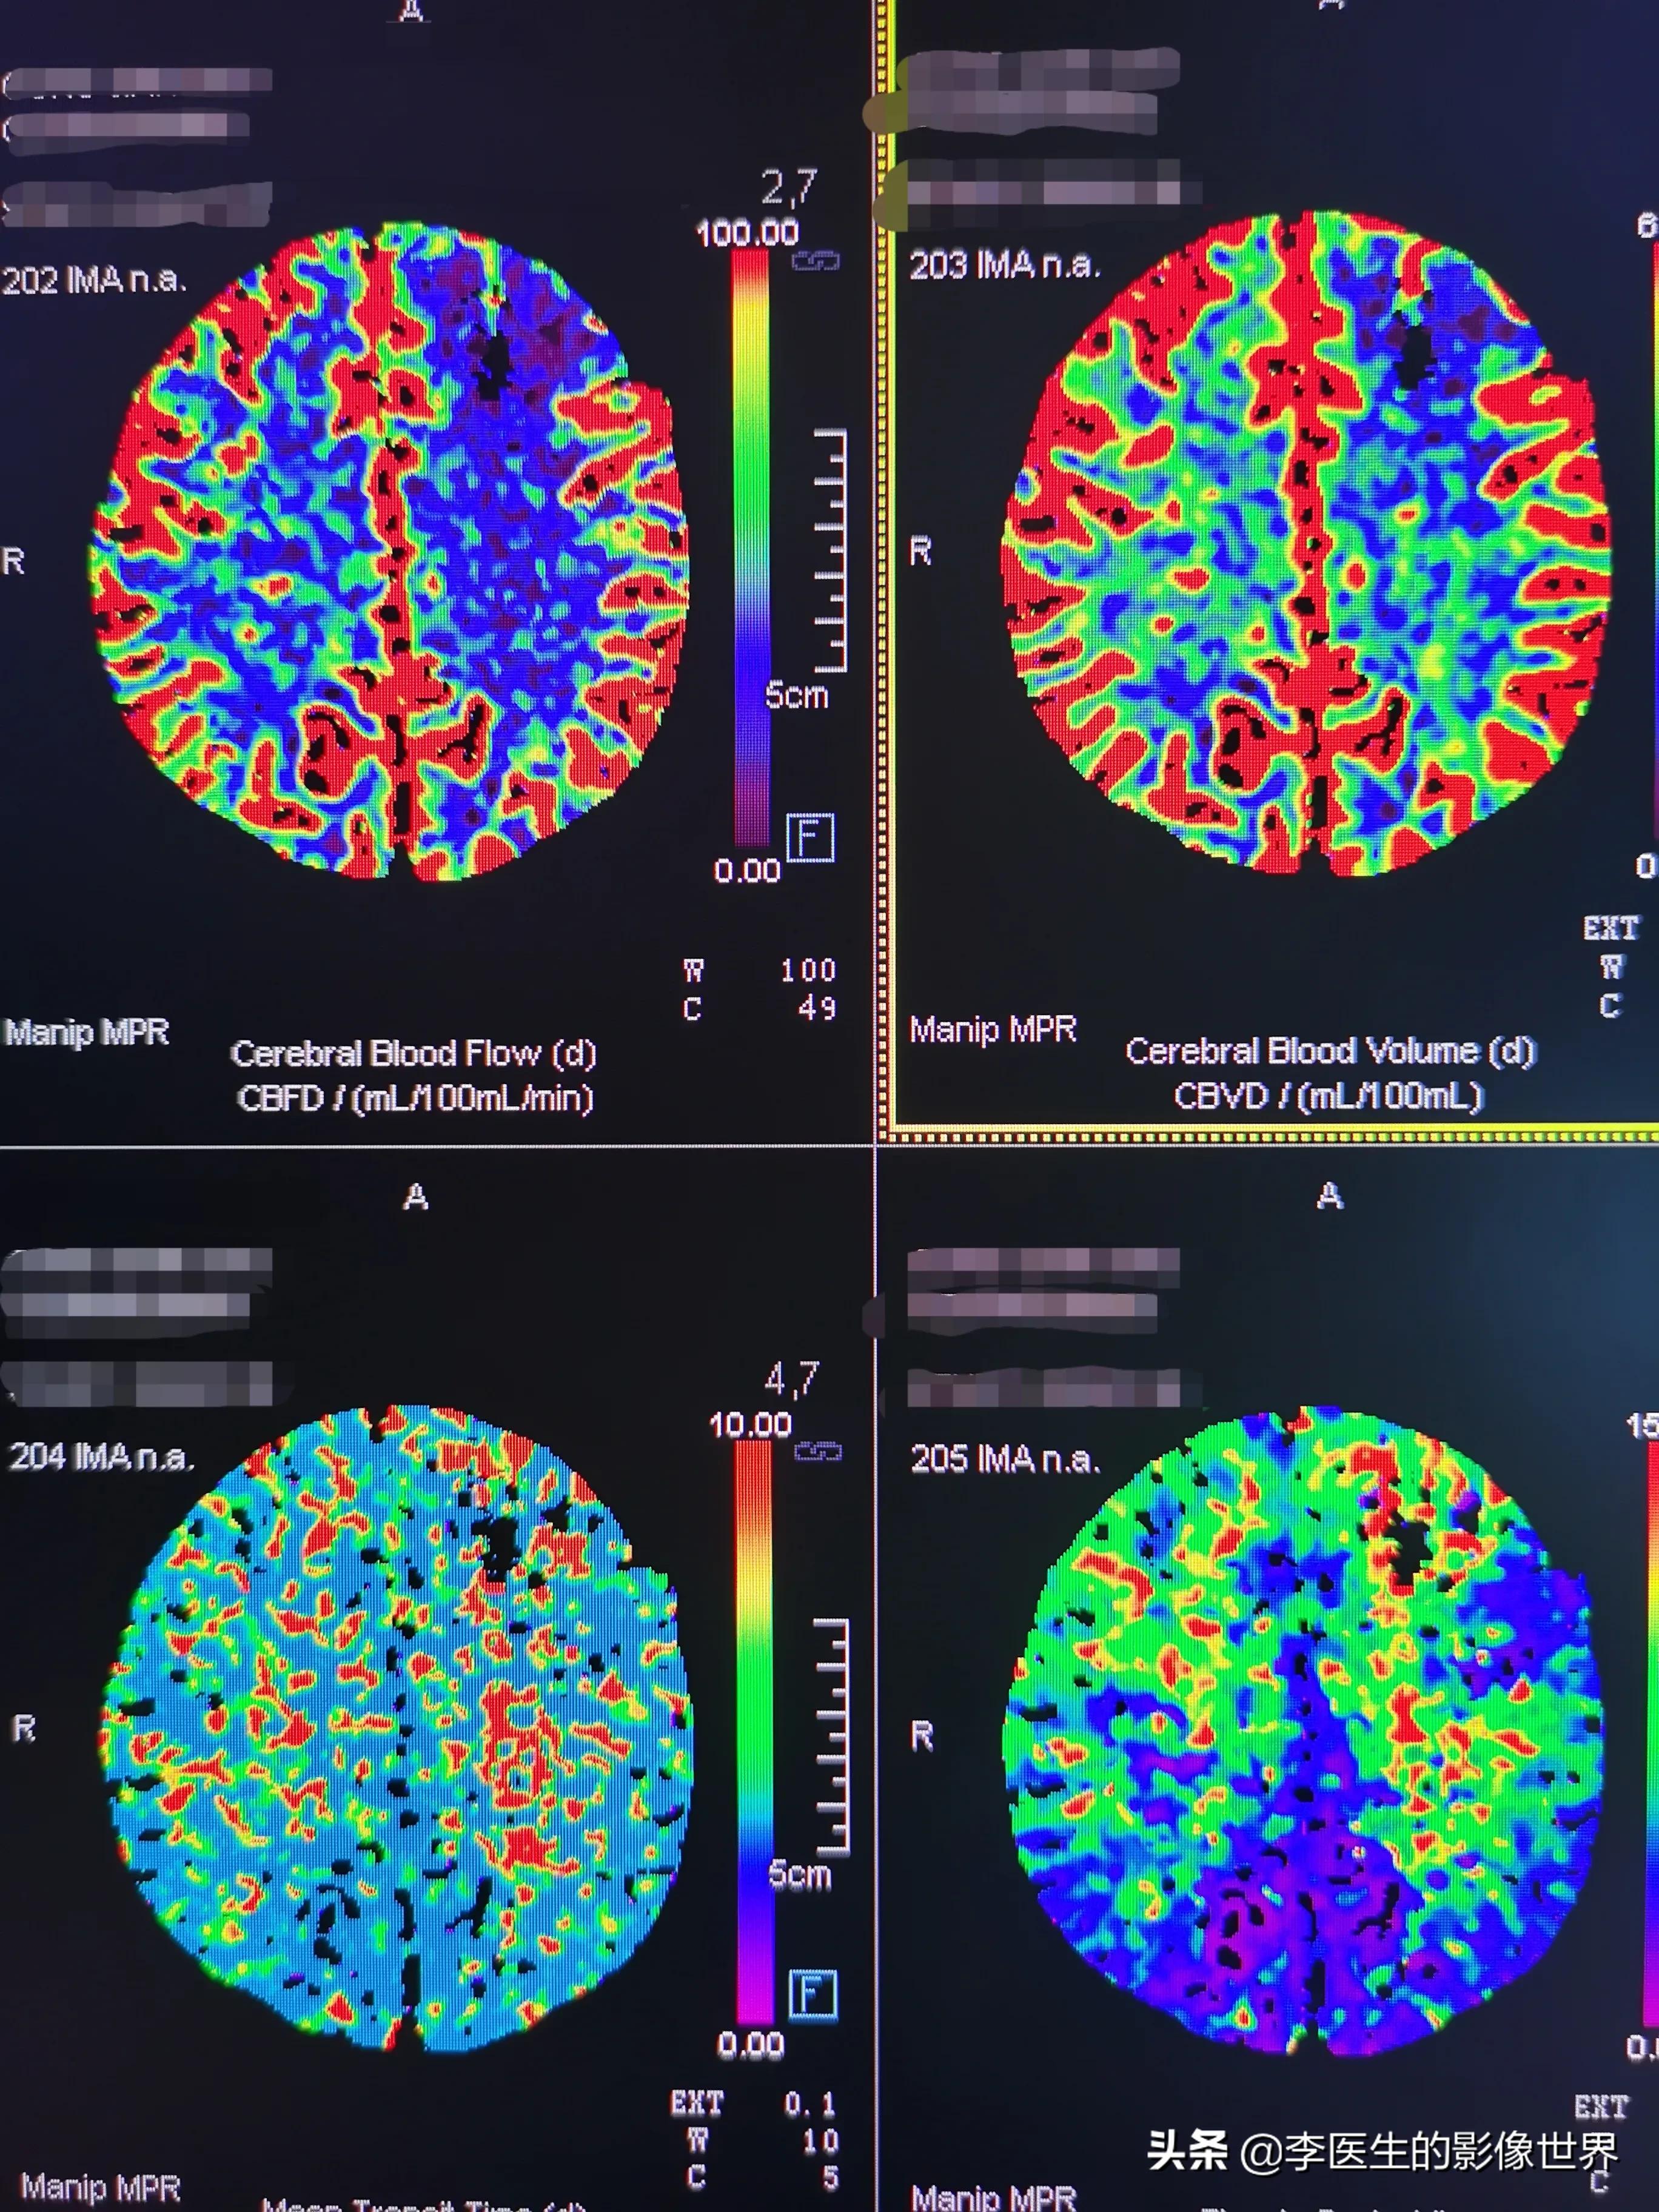

图1上面2图为CBF(脑血流量)、CBV(脑血容量),下面2图为平均达峰时间(MTT)、达峰时间(TTP)。

再看灌注,左额叶梗死区四个参数均异常,不可逆梗死,这块地没救了,先不理它,看剩下大片土地。

CBF、CBV余部双侧大脑血流、血容量均无明显减低,稍不均匀。说明田地每日供水量、土地含水量基本正常。

MTT、TTP双侧额顶叶(大脑前、中动脉供血区)值升高其中TTP额叶升高更明显。说明大渠(大脑中)虽然堵了,可是开通了很多小渠(侧枝代偿),也基本够灌溉,只是灌溉速度不如大渠那么快,费些时间。

因为额叶的沟渠更细小。甚至可能是不够用,只是脑梗死后再灌注及旁路移植(开多了一些小水渠)后灌溉量上去了,所以CBF、CBV趋向正常,然而刚开的渠道显然长期开放的渠道(大脑中侧枝)那么顺畅好用,因而灌溉仍旧慢了些。

CBV是预测脑梗死的指标,CBV降低,迟早会发生脑梗,就是土地含水量不足,粮食肯定会减产。